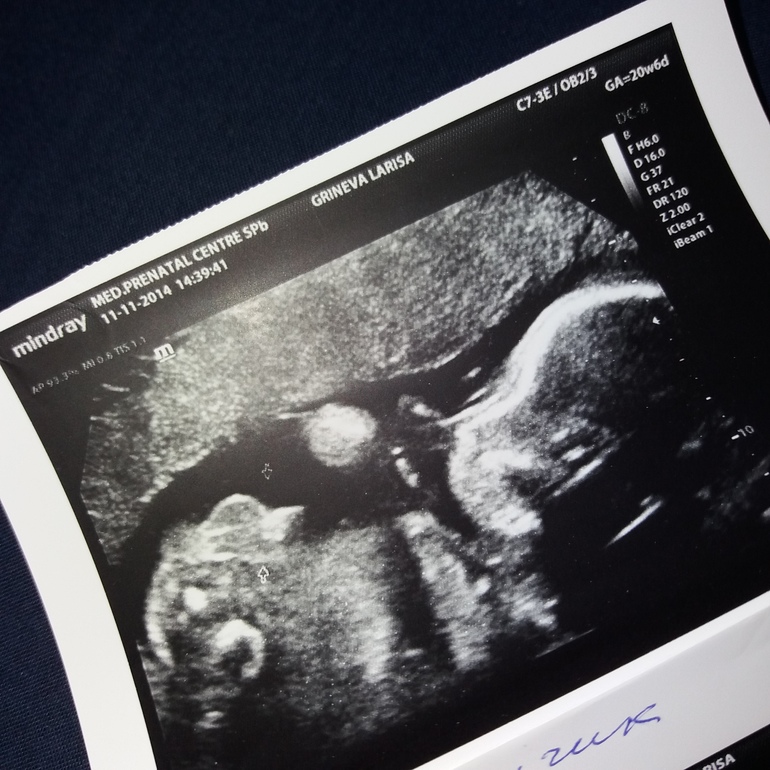

Ульяна в Здоровье будущей мамы 8 лет Какой пол? Вопросы про УЗИ, обследования и анализы: что, где, как, когда? 20 недель.Вид на попу и ножки снизу Посмотрите еще 20 записей на эту тему Отменить Ответить Юлия Девочка) 08.05.2018 Ответить Ольга Девочка 07.05.2018 Ответить Ларёк У меня вот такой снимок, тут и без врача понятно... А Вам что врач сказал? 07.05.2018 Ответить Катрина Еще где- то делают такие снимки? Вообще ничего непонятно,здесь если только врач различит и то вряд ли.) 07.05.2018 Ответить Анечка Снимок хуже не придумать. Врач то сам что сказал? 07.05.2018 Ответить Йожик ♀ - геноцид имбецилов Один из двух,однозначно 07.05.2018 Ответить Дане4ка Больше на девочку похоже. Но видно плохо. 07.05.2018 Ответить Светлана Девочка 07.05.2018 Ответить Xatulya Не понятно что где вот вообще.. 07.05.2018 Ответить Дарья Не вижу ни попу ни ножки ни собственно пол.. вообще не вижу . 07.05.2018 Ответить УЗИ 5 недель не просматривается эмбрион Чаты Беременных Выберите чат: Январята-2026 Февралята-2026 Мартята-2026 Апрелята-2026 Майчата-2026 Июнята-2026 Июлята-2026 Августята-2026